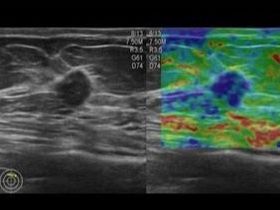

超音波診断装置 乳腺超音波検査 心臓超音波検査

ARIETTA 850

⑤ 超音波検査

乳腺・甲状腺(良性および悪性腫瘤・その他異常所見の有無)、頸動脈(動脈硬化等による血管の

詰まりや血流)、心臓(弁を含めた心臓の動き)を画像として捉え検査します。また、女性技師による乳がんドック(乳腺超音波検査)行っております。詳しくはこちら